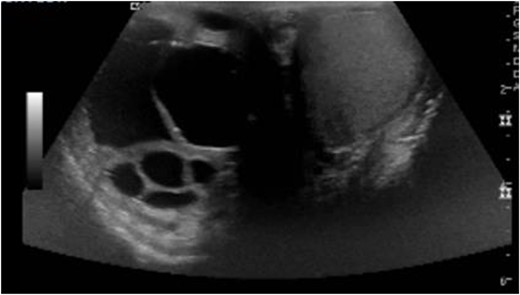

A 44-year-old male with a past medical history of alcohol abuse presented to the emergency department with 2 days of right upper quadrant abdominal pain and vomiting. The patient was reported to have hematemesis prior to arrival. The patient was unable to give a comprehensive history due to altered mental status and was noted to be diaphoretic, pale and hypotensive on arrival. Hemoglobin, hbg, was noted to be 10.1 upon arrival; however, subsequent hbg was 5.3. Bedside arterial blood gas showed significant metabolic acidosis with a pH of 7.03 and lactic acid of 11. Massive transfusion protocol was started and vasopressor therapy was initiated. Bedside Focused Assessment with Sonography in Trauma, FAST, exam was performed and positive for fluid in the right upper quadrant. At this time, the patient had been stabilized and the decision was made to obtain a computed tomography angiography (CTA) of the chest, abdomen and pelvis. CTA revealed hemoperitoneum anterior to the left lobe of the liver, a large para-aortic and aortocaval mass with peripheral enhancement suggesting neoplastic adenopathy, measuring 5.2 × 8.1 cm, and a complex septated lesion in the right scrotum (Fig. 1A and B).

(A, B) CTA shows hemoperitoneum anterior to the left lobe of the liver.